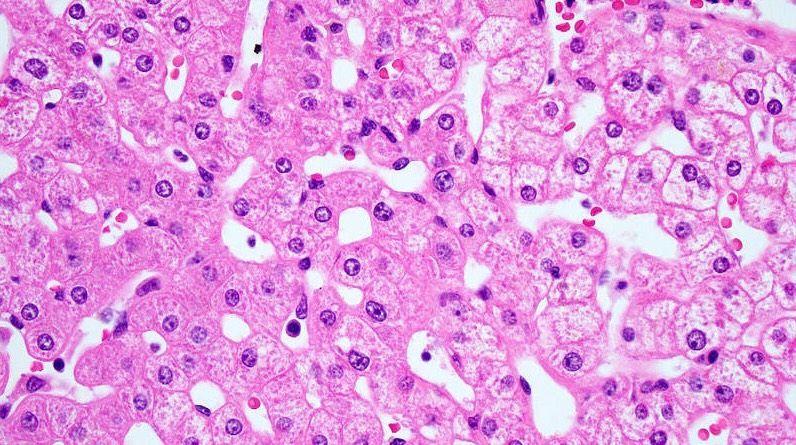

In this project, we are applying deep learning methods to images of H&E-stained tissue slides collected after exposing rodents to carcinogens to investigate mutagenic and non-mutagenic modes-of-action at a spatially-resolved, single-cell level. This project is in collaboration with the United States NIEHS and the Coorens Lab at EMBL-EBI.